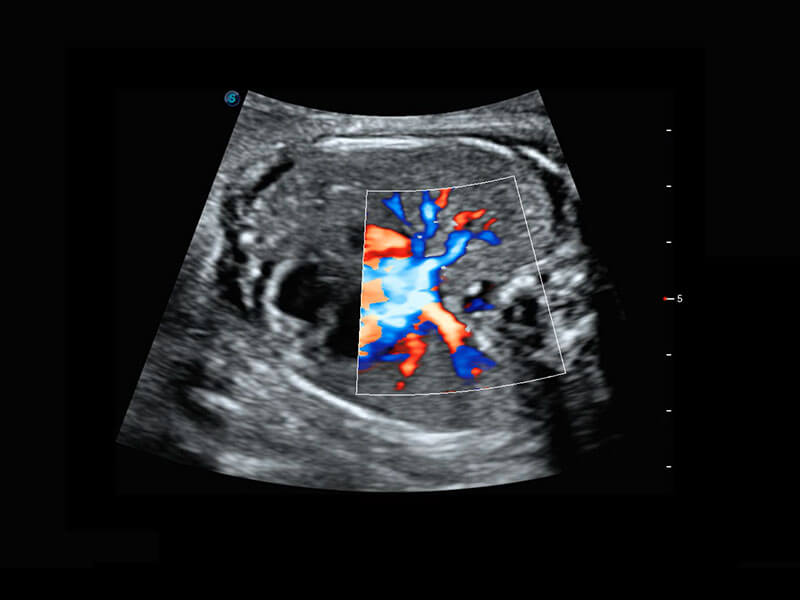

P60优异的图像质量搭载专科探头,在妇科基础疾病的诊断、卵泡生长的监测、输卵管通畅情况的判别等方面为您提供生殖应用方案。

胎儿体循环